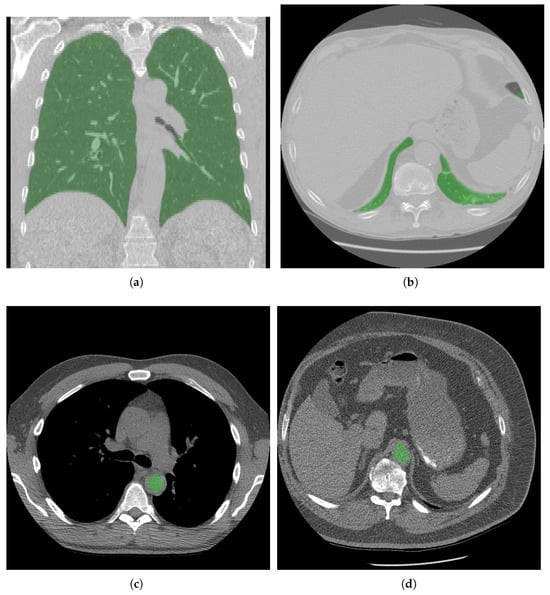

Low-Dose CT Quality Assurance at Scale: Automated Detection of Overscanning, Underscanning, and Image Noise

Automated quality assurance is essential for low-dose computed tomography (LDCT) lung screening, yet manual checks strain clinical workflows. We present a fully automated artificial intelligence tool that quantifies scan coverage and image noise in LDCT without user input. Lungs and the aorta are segmented to measure cranial/caudal over- and underscanning, and noise is computed as the standard deviation of Hounsfield units (HUs) within descending aortic blood, normalized to a 1 mm3 voxel. Performance was verified in a reader study of 98 LDCT scans from the National Lung Screening Trial (NLST), and then applied to 38,834 NLST scans reconstructed with a standard kernel. In the reader study, lung masks were rated ≥“Nearly Perfect” in 90.8% and aorta-blood masks in 96.9% of cases. Across 38,834 scans, mean overscanning distances were 31.21 mm caudally and 14.54 mm cranially; underscanning occurred in 4.36% (caudal) and 0.89% (cranial). The tool enables objective, large-scale monitoring of LDCT quality—reducing routine manual workload through exception-based human oversight, flagging protocol deviations, and supporting cross-center benchmarking—and may facilitate dose optimization by reducing systematic over- and underscanning. Full article